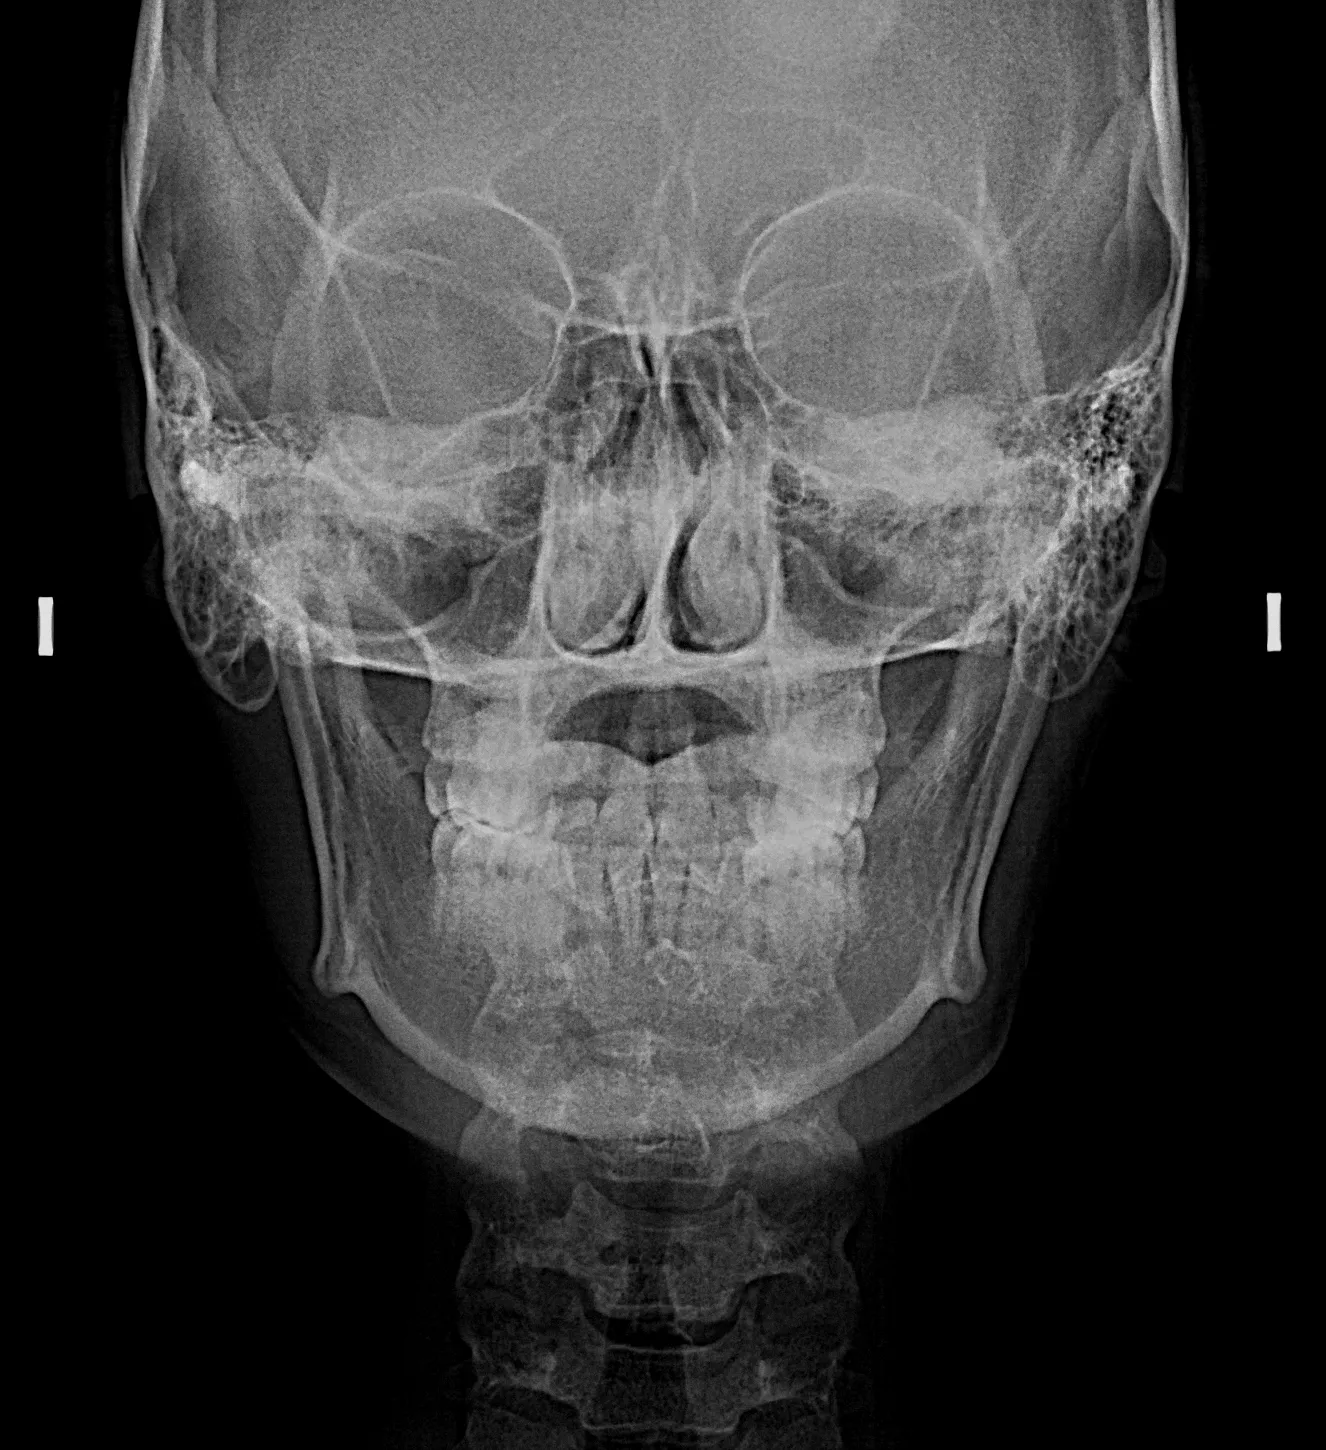

Radiografías Extraorales

Las radiografías extraorales permiten obtener imágenes completas de los maxilares, la articulación temporomandibular (ATM) y las estructuras faciales sin colocar el sensor dentro de la boca.

Realizamos estudios como radiografía panorámica, cefalométrica, de senos paranasales y de ATM, esenciales para tratamientos de ortodoncia, cirugía y diagnóstico integral.